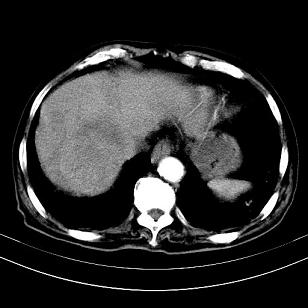

标题: CT19407:肝内还是肝外原发性肿瘤??

男,63岁,高血压病史40余年,

考虑右肝后叶肝癌(部分外生)伴肝内多发性转移;右侧肾上腺区恶性肿瘤并肝转移待排。

支持肝癌肝内转移,肝硬化。

支持肝右叶巨块型肝癌伴肝内转移.

支持肝右叶巨块型肝癌伴肝内转移。